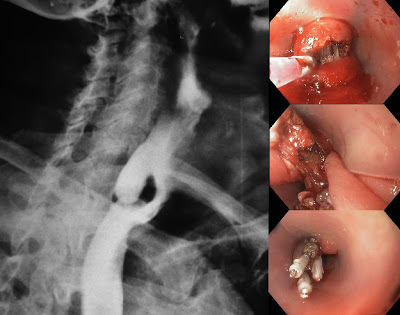

Paciente idoso com disfagia, halitose, regugirtação, massa palpável à esquerda em pescoço que alivia a compressão, e história de pneumonias por broncoaspiração…

Divertículo de Zenker

Esofagografia baritada

O que é o Divertículo de Zenker?

Hipertonia do EES sobre o m. cricofaringeo, o que faz o m. tireofaríngeo contrair mais forte, aumentando pressão esofágica, gerando o divertículo na região do trígono de Killian

Como é o tratamento do divertículo de Zenker?

< 2 cm: miotomia do EES

> 2cm: miotomia + diverticulopexia (fixar)

> 3cm: EDA (miotomia + diverticulotomia)

> 5cm: miotomia + diverticulectomia (retirar)

*miotomia = cricofaringomiotomia